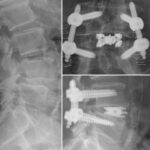

dualX®Slim transforms the fusion environment from insertion to spinal restoration by delivering a powerful dual-expanding implant through a minimally-invasive or endoscopic approaches. dualX®Slim has one of the smallest insertion profiles in the market while still expanding in both horizontal and vertical directions to provide an ALIF-sized final geometry with higher degrees of lordosis (8°, 12°, 15°, 18°*) through the patented trueLordosis™ technology.

10 mm Insertion Width

Lateral expansion establishes stable footprint Large, center bone graft chamber for post-expansion grafting

20 mm Fully Expanded Width

Powerful vertical expansion restores disc height for decompression

Vertical expansion assists in direct and indirect decompression Multiple lordotic angles restore sagittal balance

8°, 12°, 15°, 18°*